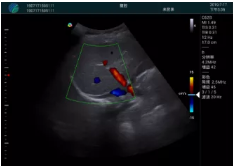

頸動脈血流充盈飽滿,無外溢

肝內血管顯示清晰,血流敏感無外溢